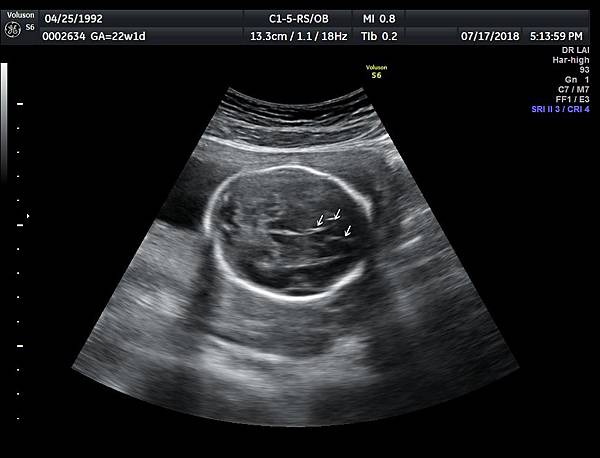

2016年8月4日在執行胎兒高層次超音波檢查時,我發現胎兒腦部的CSP(cavum septum pellucidum)很不清楚(附圖1~4),遇到這種情況,需要仔細評估胎兒腦部的駢胝體,因為CSP的天花板是駢胝體,CSP不明顯時,要合理的懷疑駢胝體沒有發育,或駢胝體下方有長東西(例如lipoma),駢胝體是連接左右大腦的神經纖維所組成。

檢查胎兒駢胝體是有技巧的,需要兩個切面:

1. 矢狀切面(sagittal plane):駢胝體呈現類似三明治的中間黑色部分,上面一層薄薄白色的區域是callosum sulcus,打上flow可以看到pericallosum artery在駢胝體上面的周圍,pericallosum artery來源是前腦動脈,參考附圖 6~10,三明治下面白白的部分是和CSP做比較得到的,如果這一層長lipoma(附圖 5),CSP很可能看不到。